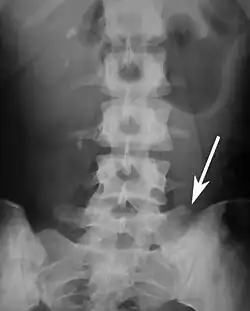

Transitional vertebrae

Transitional vertebrae have the characteristics of two types of vertebra. The condition usually involves the vertebral arch or transverse processes. It occurs at the cervicothoracic, thoracolumbar, or lumbosacral junction. For instance, the transverse process of the last cervical vertebra may resemble a rib. A transitional vertebra at the lumbosacral junction can cause arthritis, disk changes, or thecal sac compression. Back pain associated with lumbosacral transitional vertebrae (LSTV) is known as Bertolotti's syndrome. One study found that male German Shepherd Dogs with a lumbosacral transitional vertebra are at greater risk for cauda equina syndrome, which can cause rear limb weakness and incontinence.[11]

The significance of transitional vertebrae has been questioned by one study finding similar prevalence in the general population as those with low back pain, [12] but more recent study found a large difference.[13]